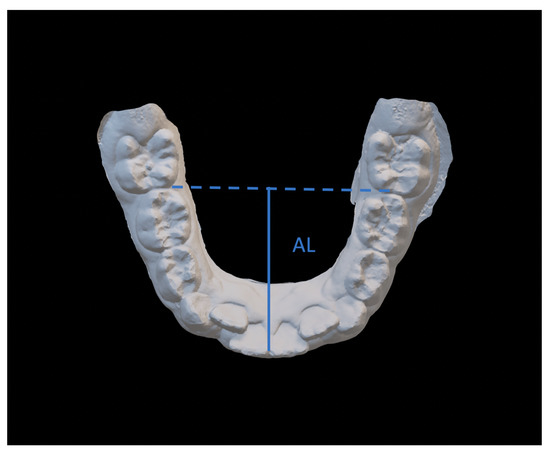

- Arch length (AL), measured as the perpendicular distance between the most vestibular point between the lower central incisors, and the connection line between the mesial contact points of the first permanent molars;